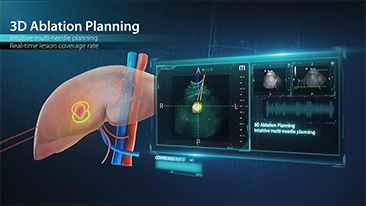

?QuĂ© tan claramente se puede ver un hĂgado?

Para las lesiones hepĂĄticas focales, como el hemangioma o el cĂĄncer de hĂgado, el diagnĂłstico por imĂĄgenes mediante ecografĂa con contraste cumple un papel importante. La tecnologĂa de diagnĂłstico por imĂĄgenes con contraste UWN+ (no lineal ultraancha) puede ayudar a obtener una mejor penetraciĂłn, una mayor relaciĂłn contraste-tejido, con un IM mĂĄs bajo y una observaciĂłn del tiempo de perfusiĂłn mĂĄs prolongada.